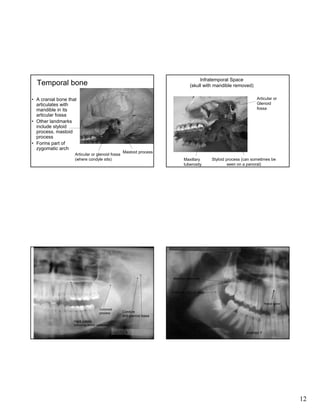

Infratemporal Space

(skull with mandible removed)

Temporal bone

Articular or

Glenoid

fossa

• A cranial bone that

articulates with

mandible in its

articular fossa

• Other landmarks

include styloid

process, mastoid

process

• Forms part of

zygomatic arch

Articular or glenoid fossa

(where condyle sits)

Mastoid process

Maxillary

tuberosity

Styloid process (can sometimes be

seen on a panoral)

Maxillary tuberosity

External oblique ridge

Nasal spine

Coronoid

Condyle

and glenoid fossa

Hard palate

(horizontal thicker radiopaque line)

Inverted Y